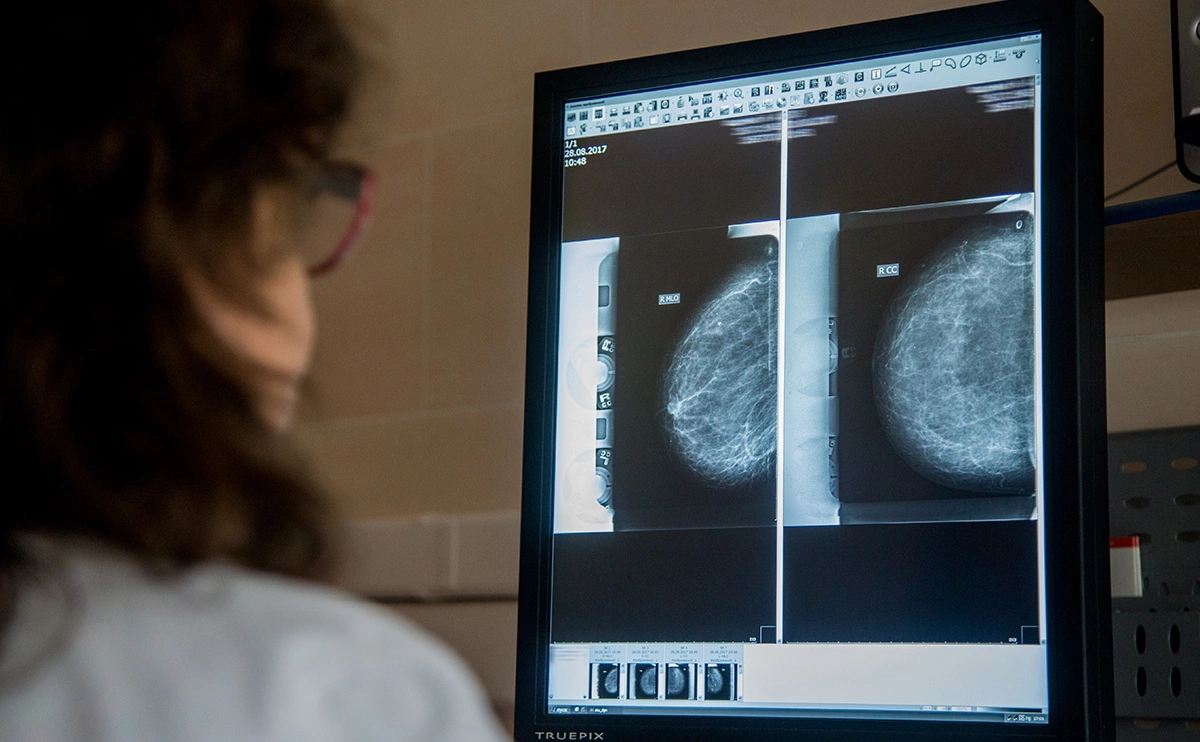

Фото: Валентина Певцова / ТАСС

Благодаря искусственному интеллекту (ИИ) столичные рентгенологи могут в восемь раз быстрее читать результаты маммографии, сообщил в своем телеграм-канале мэр Москвы Сергей Собянин.

По словам главы города, обычно маммографические снимки анализируют два специалиста, что позволяет избежать ошибок. Кроме того, двойное чтение изображений делает оценку независимой и качественной. Однако если анализ проводится с помощью нейросети, то качество диагностики остается таким же высоким, а время проведения существенно сокращается.

Мэр отметил, что на данный момент рентгенологам помогают около 50 сервисов искусственного интеллекта. «Нейросети наносят на снимки цветовую разметку и производят измерения. Алгоритм определяет на изображениях признаки рака легкого, COVID-19, инсульта, ишемической болезни сердца и других заболеваний, — уточнил градоначальник. — Тем не менее последнее слово всегда остается за специалистом».